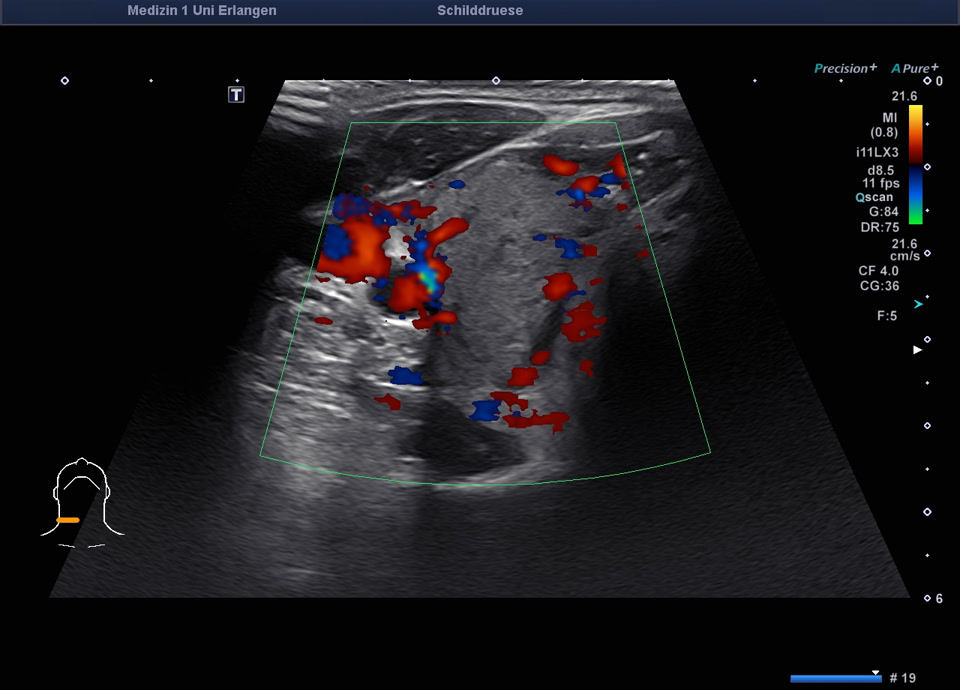

45-year-old male presented patient with persistent sore throat and general symptoms following an EBV-infection. An external diagnosis of post-infectious de Quervain’s thyroiditis had already been made, and a two-week course of corticosteroid therapy was administered. Initial clinical improvement with reduced throat pain was noted under treatment, but symptoms reoccurred after discontinuation of corticosteroids. Laboratory findings revealed leukocytosis of 12,000/µl and CRP of 113 mg/l. Sonographically, a bilaterally enlarged thyroid gland with diffusely hypoechoic areas and inhomogeneous parenchyma was observed. Combined with the patient history, this was characteristic of a subacute thyroiditis with relapse after short-term corticosteroid therapy. Prolonged corticosteroid therapy with slow tapering was performed. Under this regimen, marked clinical improvement occurred within weeks; follow-up ultrasound four months later showed a normal-sized thyroid with only mildly inhomogeneous parenchyma, consistent with resolving thyroiditis.